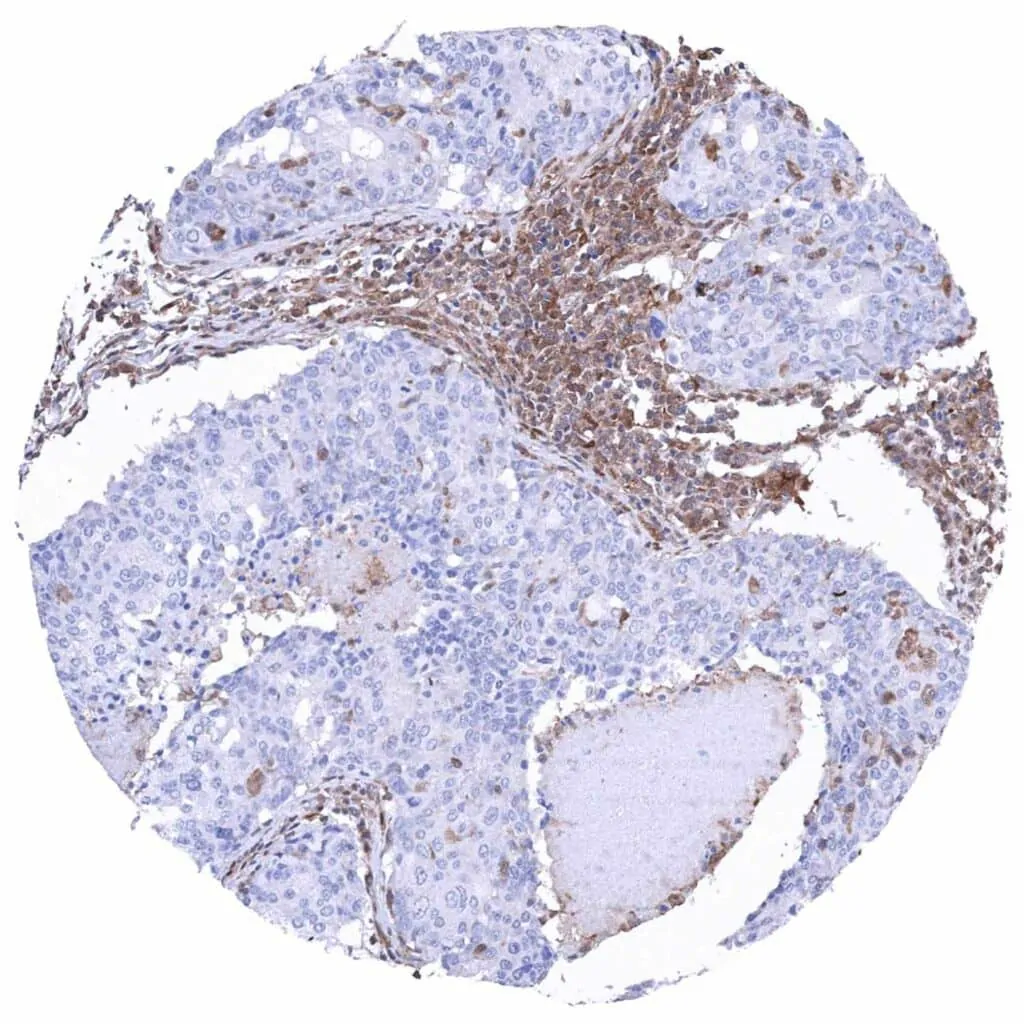

Ovary – Serous high-grade carcinoma with complete absence of MTAP staining in tumor cells. Significant MTAP staining of inflammatory and stromal cells